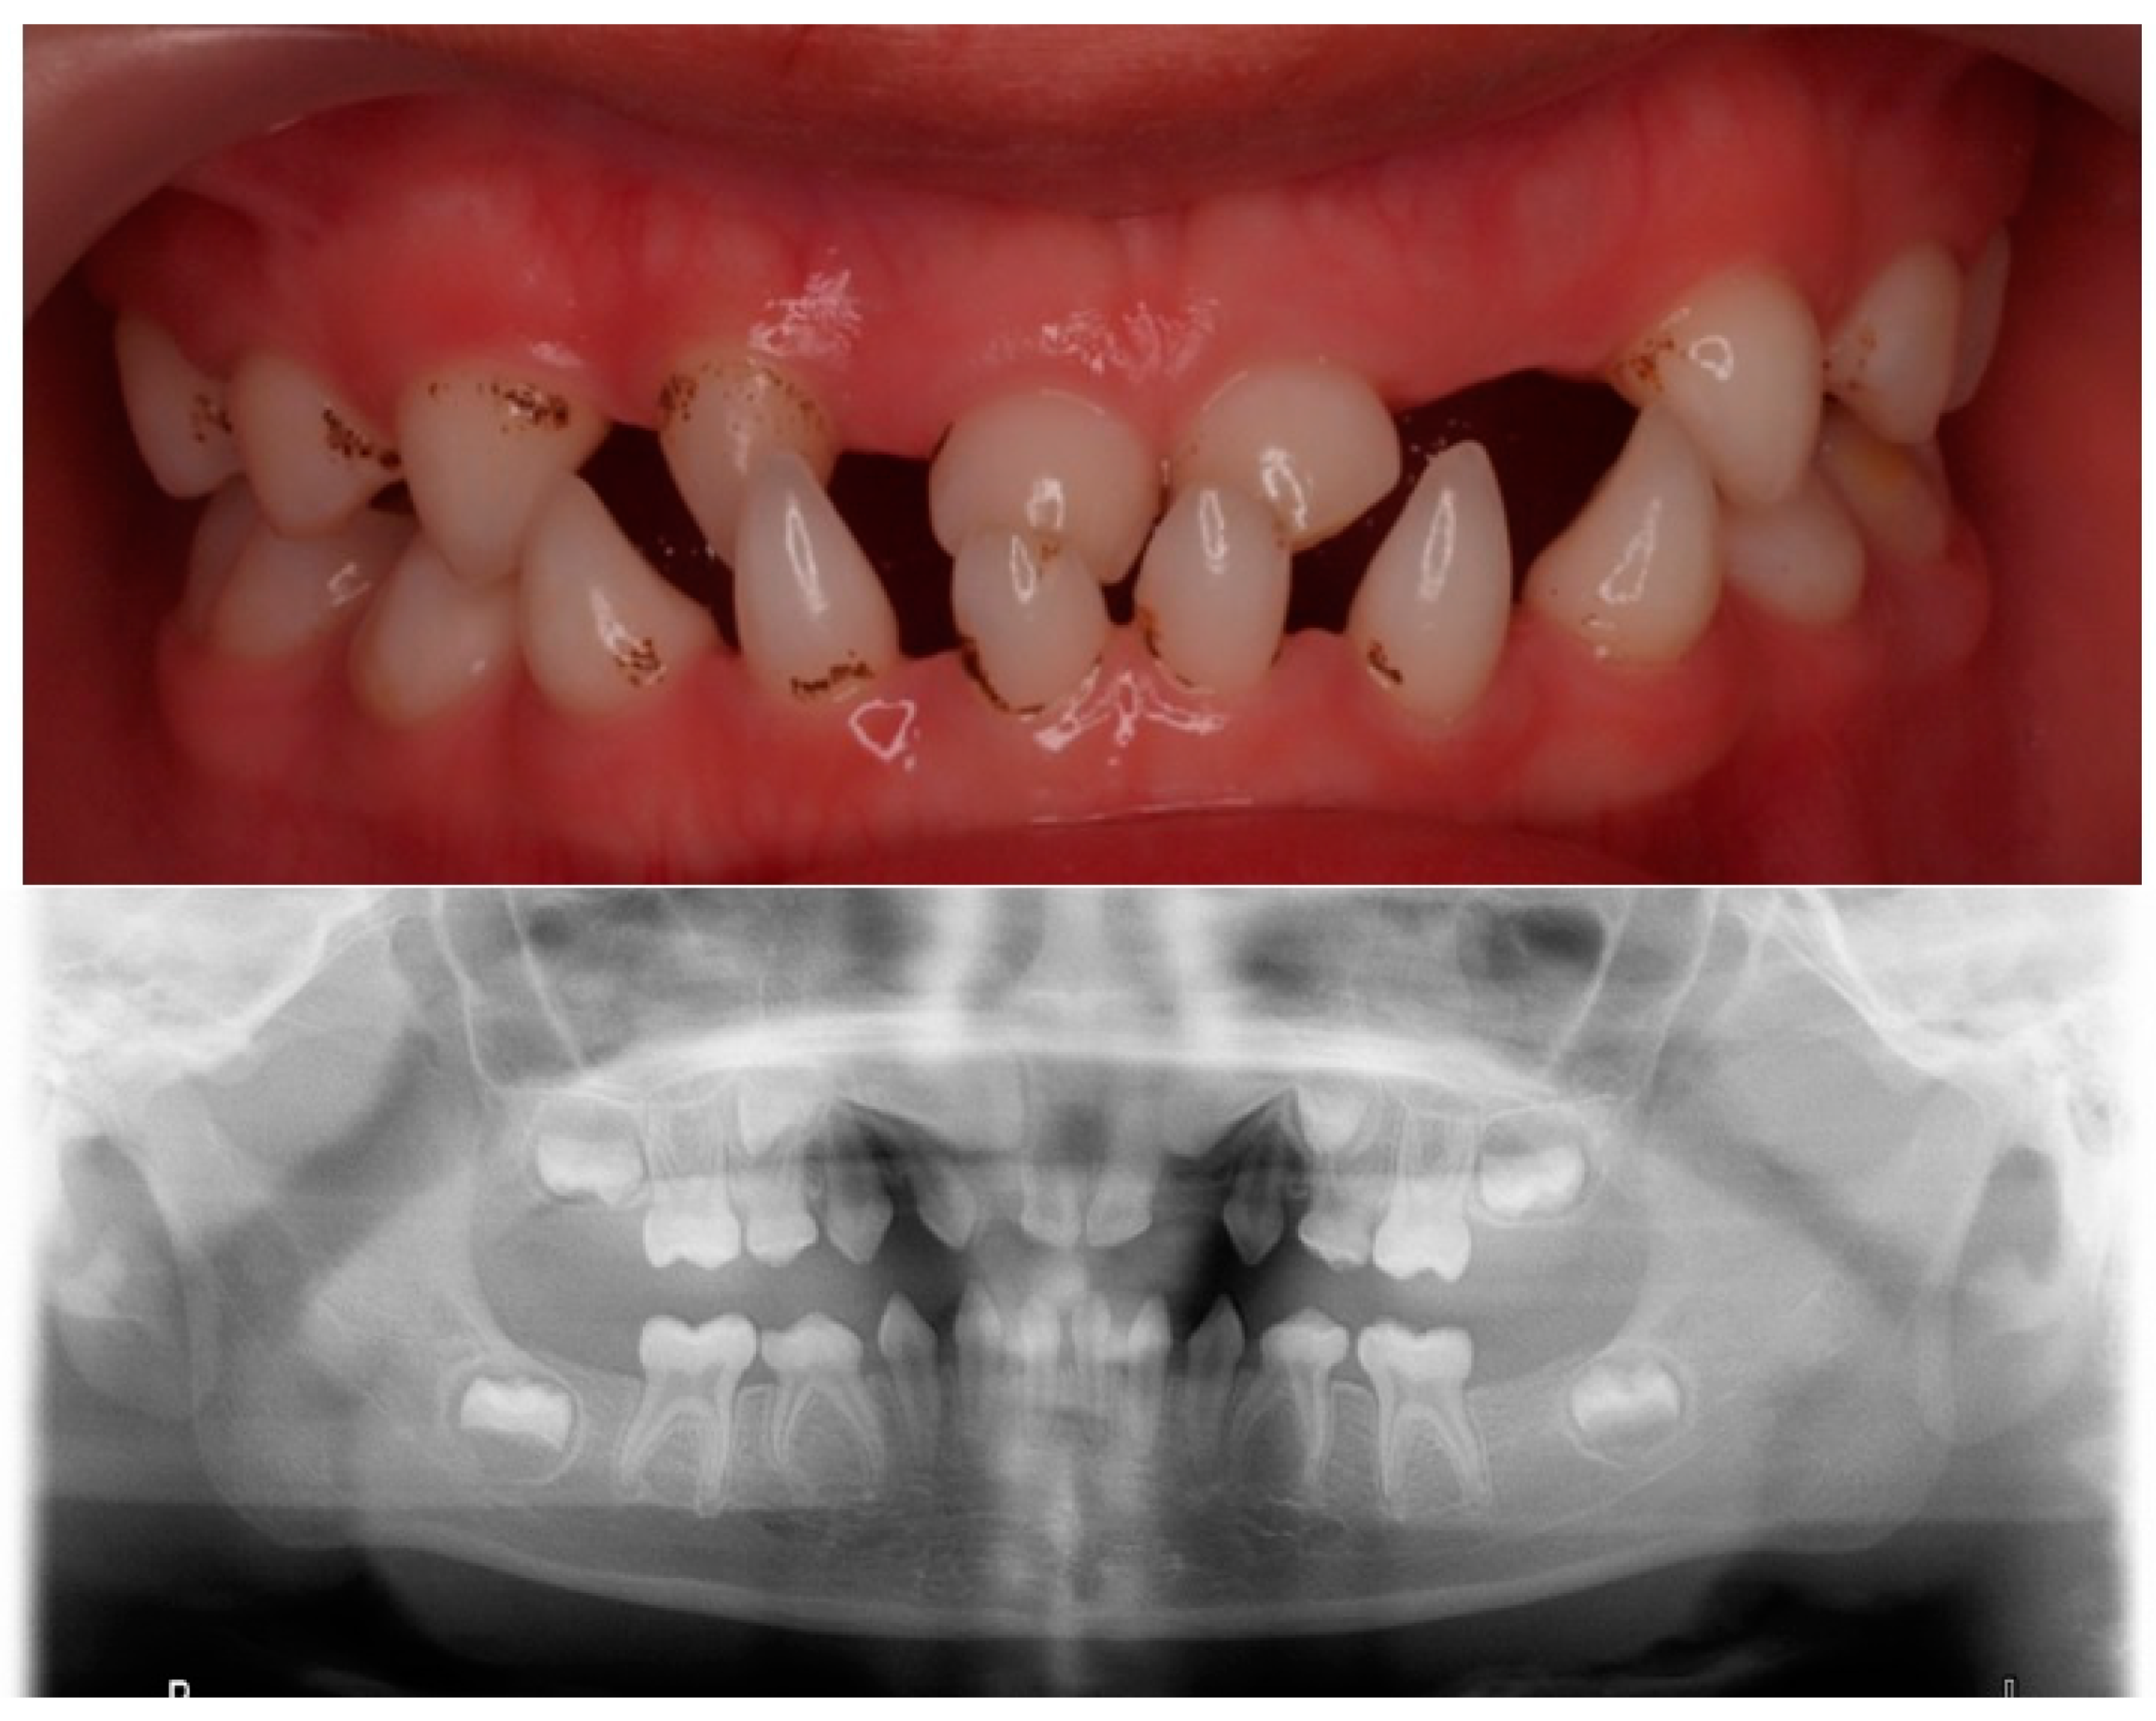

Figure 2.

Clinical and radiographical findings at 6 years old.

In a new dental visit, at the age of 6 years, an orthopantomography was performed, where multiple agenesis was observed in both the primary and permanent dentition. Given that more than six permanent teeth were missing, it was labelled as oligodontia [14] (Figure 2). He also had a comprehensive phenotypic evaluation, and a genetic study was performed.